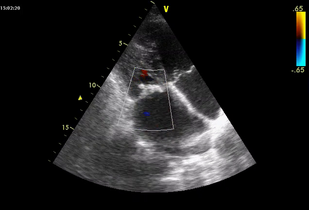

• Обложка: Ревматический митрально-аортальный порок сердца с преобладанием митрального стеноза (рис. 7.7)